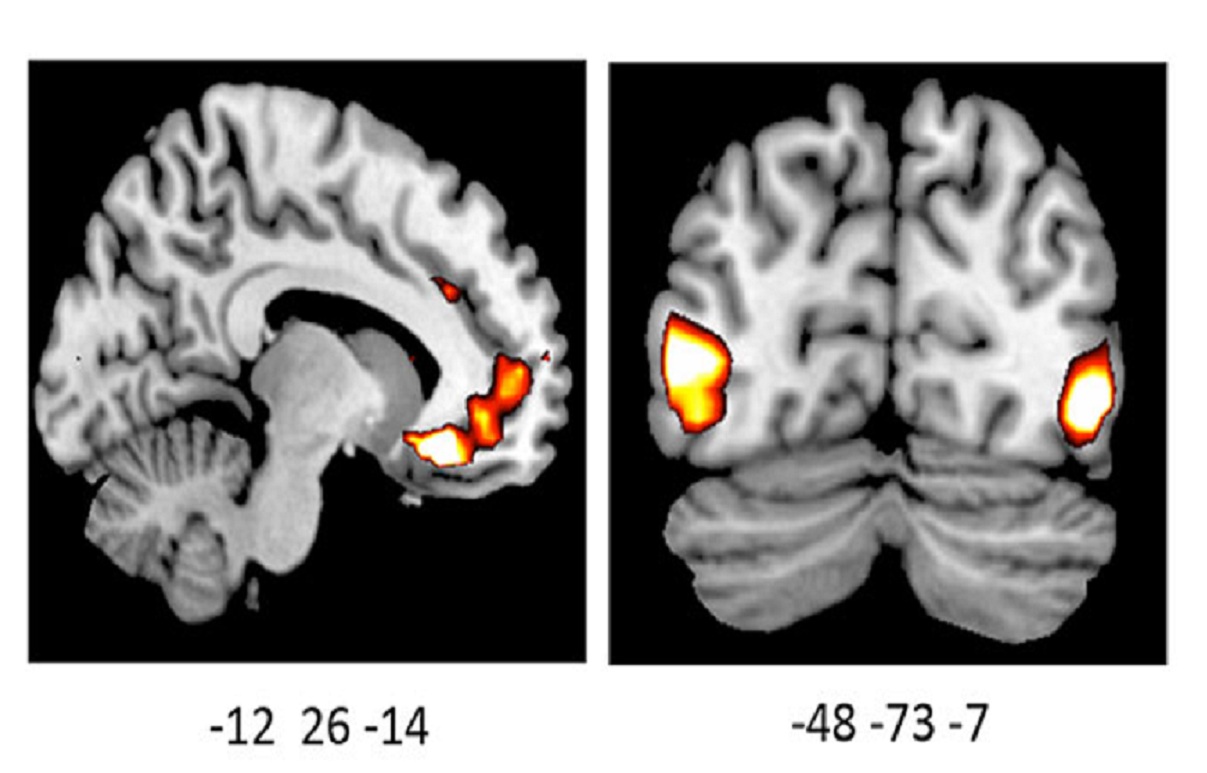

La imagen muestra una actividad incrementada en los cerebros de los portadores de la variante por delación del gen ADRA2b. Fuente: UBC.

El estudio, publicado recientemente en The Journal of Neuroscience, reveló que los portadores de una determinada variación genética percibían imágenes positivas y negativas con mayor intensidad, y presentaban una actividad cerebral aumentada en ciertas regiones del cerebro ante dichas imágenes.

La investigadora analizó los cerebros de 39 participantes, 21 de los cuales eran portadores de la variación genética.

De todos los voluntiarios, los portadores de dicha variación mostraron significativamente más actividad en una región del cerebro responsable de la regulación de las emociones, y de la evaluación tanto del placer como de la amenaza.